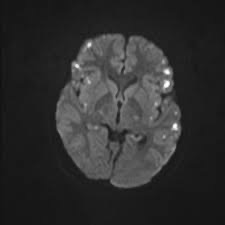

前述の通り、本病態は大-小動脈が段階的/多発性に障害されるという特徴があります。そのため病変は皮髄境界に好発し、多発・両側性で時間差で増加してくるような経過をとります。MRAでは分節状狭窄や後拡張を認めることがあります。素人目には、若年者や血管リスクが高くない患者なのに、MRAで血管ボロボロという感じに見えます。

② 頭部MRIで背景の血管リスクに比してひどい多発脳梗塞/血管障害

・皮疹の病歴は1/3の症例では認めず、皮髄境界の多発梗塞や血管狭窄などの画像所見が重要